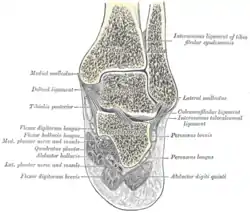

Coronal cross-section through the right ankle showing the lateral malleolus (right) and medial malleolus (left) | |

Each leg is supported by two bones, the tibia on the inner side (medial) of the leg and the fibula on the outer side (lateral) of the leg. The medial malleolus is the prominence on the inner side of the ankle, formed by the lower end of the tibia. The lateral malleolus is the prominence on the outer side of the ankle, formed by the lower end of the fibula.

Medial malleolus

The medial malleolus is found at the foot end of the tibia. The medial surface of the lower extremity of tibia is prolonged downward to form a strong pyramidal process, flattened from without inward - the medial malleolus.

- The medial surface of this process is convex and subcutaneous.

- The lateral or articular surface is smooth and slightly concave, and articulates with the talus.

- The anterior border is rough, for the attachment of the anterior fibers of the deltoid ligament of the ankle-joint.

- The posterior border presents a broad groove, the malleolar sulcus, directed obliquely downward and medially, and occasionally double; this sulcus lodges the tendons of the Tibialis posterior and Flexor digitorum longus.

- The summit of the medial malleolus is marked by a rough depression behind, for the attachment of the deltoid ligament.

Lateral malleolus

The lateral malleolus is found at the foot end of the fibula, of a pyramidal form, and somewhat flattened from side to side; it descends to a lower level than the medial malleolus.

- The medial surface presents in front a smooth triangular surface, convex from above downward, which articulates with a corresponding surface on the lateral side of the talus. Behind and beneath the articular surface is a rough depression, which gives attachment to the posterior talofibular ligament.

- The lateral surface is convex, subcutaneous, and continuous with the triangular, subcutaneous surface on the lateral side of the body.

- The anterior border is thick and rough and marked below by a depression for the attachment of the anterior talofibular ligament.

- The posterior border is broad and presents the shallow malleolar sulcus, for the passage of the tendons of the Peronæi longus and brevis.

- The summit is rounded and gives attachment to the calcaneofibular ligament.